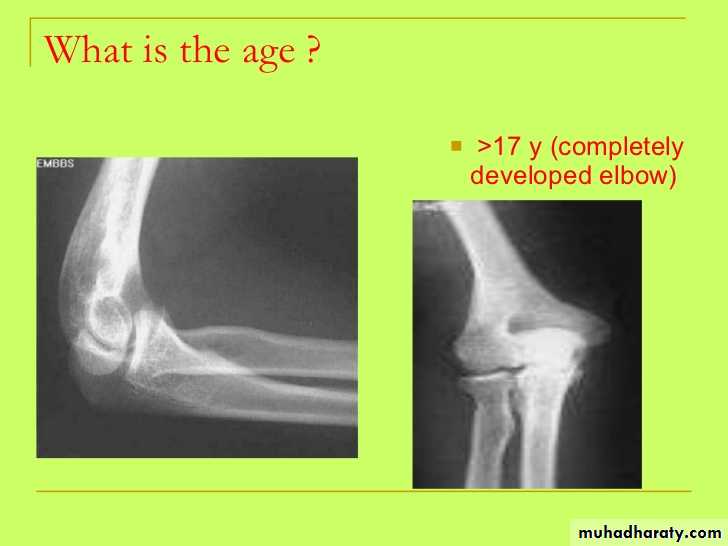

• عمليا يتم تصوير الرسغ والمرفق والكتف لمن يبدوا ظاهرا دون سن العشرين عاما من العمر. ويصور الحرقف لمن بدا في اواسط العقد الثالث من العمر او اقل, والنهاية الانسية للترقوة والتحام القص بالرهابة لمن تجاوز ذلك.

معدل التحام مراكز التعظم:

1) في سن 13-14 سنة تلتحم البكرة بعمد العضد.

2) في سن 14-15 يلتحم راس الكعبرة بالعمد والنتوء المرفقي بالزند.

3) في سن 16-17 سنة تلتحم اللقمة الانسية بعمد العضد.

574) في سن 17-18 تلتحم النهايتان السفليتان للكعبر والزند كل مع عمده.

5) في سن 18-19 يلتحم راس العضد بعمده.

6) وفي سن 25 سنة يلتحم عرف الحرقف بالحرقف والنهاية الانسية للترقوة بالترقوة.